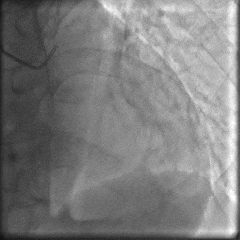

冠脉造影:

▶ LM未见明显狭窄;LAD近中段狭窄60%;LCX未见明显狭窄;RCA细小,未见明显狭窄。